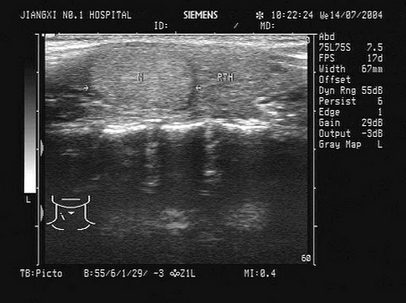

某患者右肾区疼痛数日,体温38℃。根据该患者右肾声像图表现,最可能的超声诊断为()

A.肾周围炎

B.肾炎

C.肾结石

D.肾结核

E.肾周血肿